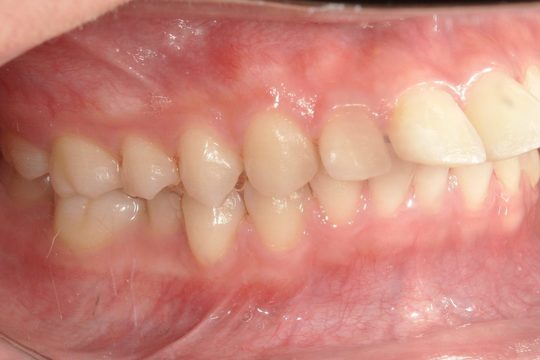

Before

浜松市中央区・自動車学校前駅のインビザラインの症例

N.T 20代女性

上の前歯が出ているのが気になる、左下の第二小臼歯が内側に入っているのが気になるとの主訴でご来院。

上の前歯を下げて左下の第二小臼歯を外に移動させることで気になっていた上顎前突を改善しました。

治療の期間:R4. 4/22〜R6. 11/2

治療の価格:66万円